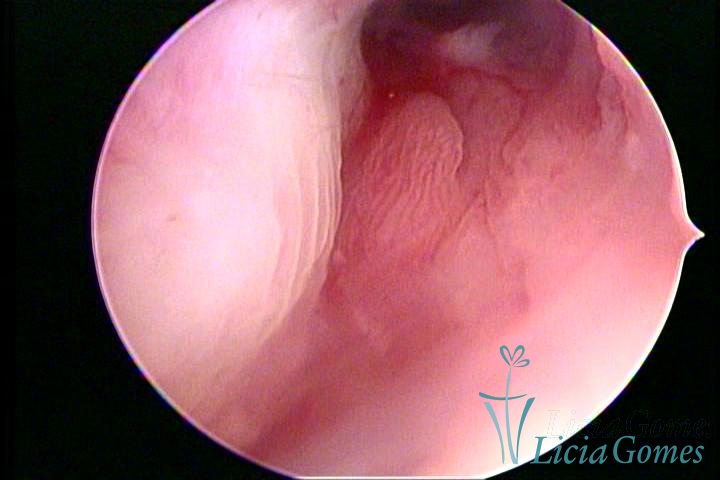

PÓLIPOS ENDOCERVICAIS

São tumores benignos, resultantes da proliferação focal reativa aos processos inflamatórios ou à situações de hiperestrogenismo, e podem ter sésseis (com a base de implantação larga) ou pediculados do epitélio.